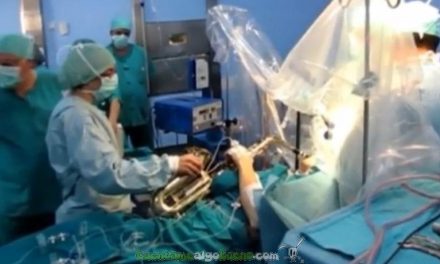

La empresa gaditana Bionaturis, en colaboración con la Universidad Pablo de Olavide, está llevando a cabo una investigación que puede revolucionar la lucha contra el cáncer. Según los expertos, las larvas de las mariposas poseen una serie de sustancias capaces de distinguir las células sanas de las cancerígenas. Para ello, más de 200.000 orugas ya están preparadas en Jerez de la Frontera para este proyecto, con objeto de reducir de forma significativa los efectos secundarios de la quimioterapia y evitar el sufrimiento del paciente.

La empresa gaditana Bionaturis, en colaboración con la Universidad Pablo de Olavide, está llevando a cabo una investigación que puede revolucionar la lucha contra el cáncer. Según los expertos, las larvas de las mariposas poseen una serie de sustancias capaces de distinguir las células sanas de las cancerígenas. Para ello, más de 200.000 orugas ya están preparadas en Jerez de la Frontera para este proyecto, con objeto de reducir de forma significativa los efectos secundarios de la quimioterapia y evitar el sufrimiento del paciente.